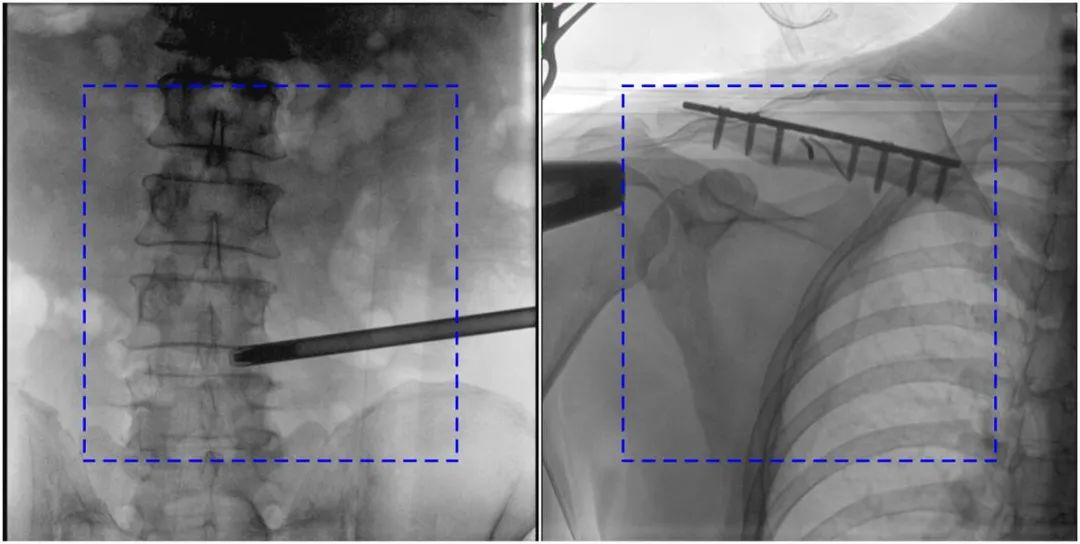

與傳統(tǒng)的21CM×21CM成像尺寸相比,普愛醫(yī)療大平板一體式C形臂具有30CM×30CM更大成像尺寸,能夠一次成像5.5節(jié)椎體,呈現(xiàn)更全面的影像信息,即便是手術經(jīng)驗不豐富的年輕醫(yī)生也能通過圖像迅速判斷椎體節(jié)段、定位手術部位,避免因為視野不足而造成的多次定位、反復曝光,提高效率的同時避免過量攝入輻射。

普愛醫(yī)療大平板一體式C形臂圖像與傳統(tǒng)圖像對比(藍色虛線內(nèi)為傳統(tǒng)21CM×21CM平板的成像區(qū)域)